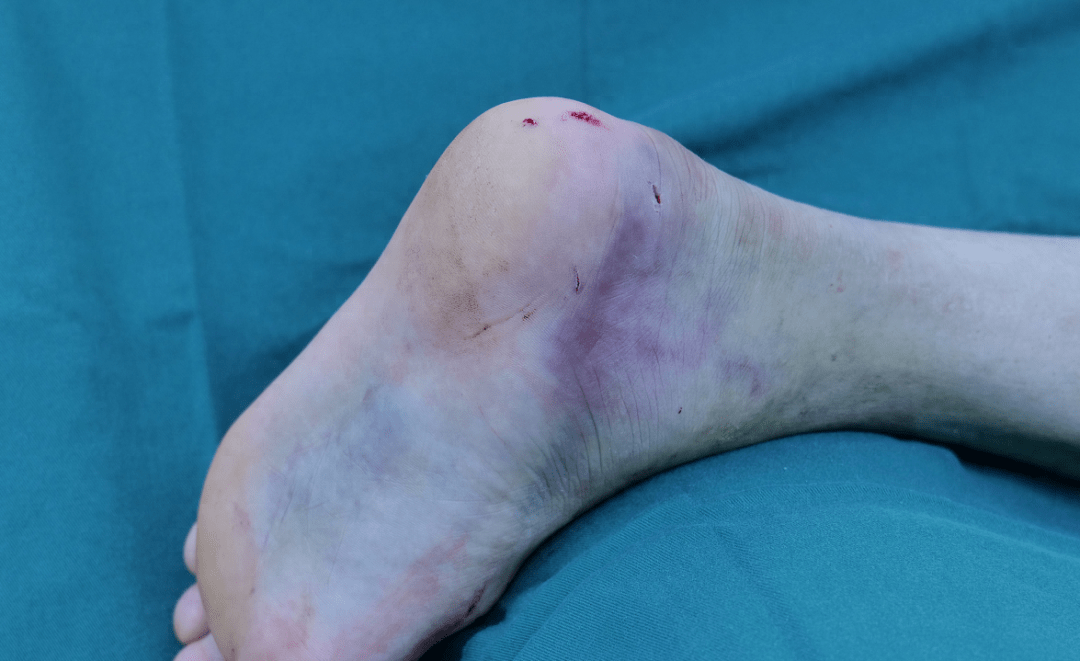

并逐步出现肿胀,皮肤青紫,后逐渐加重,来到我院就诊,诊断为左跟骨骨折